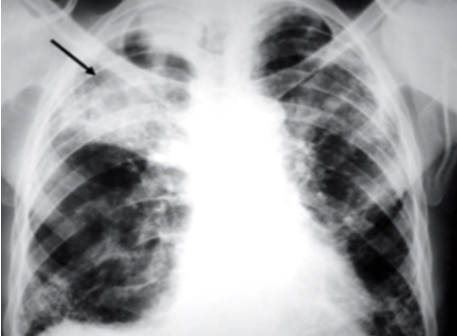

Síndrome de Caplan (Pneumoconiose Reumatoide)

Uma manifestação rara onde ocorre a combinação de Pneumoconiose (Silicose ou Carvão) + Artrite Reumatoide.

- Imagem: Nódulos pulmonares periféricos, múltiplos, de evolução rápida e grandes (1 a 5 cm), podendo cavitar.